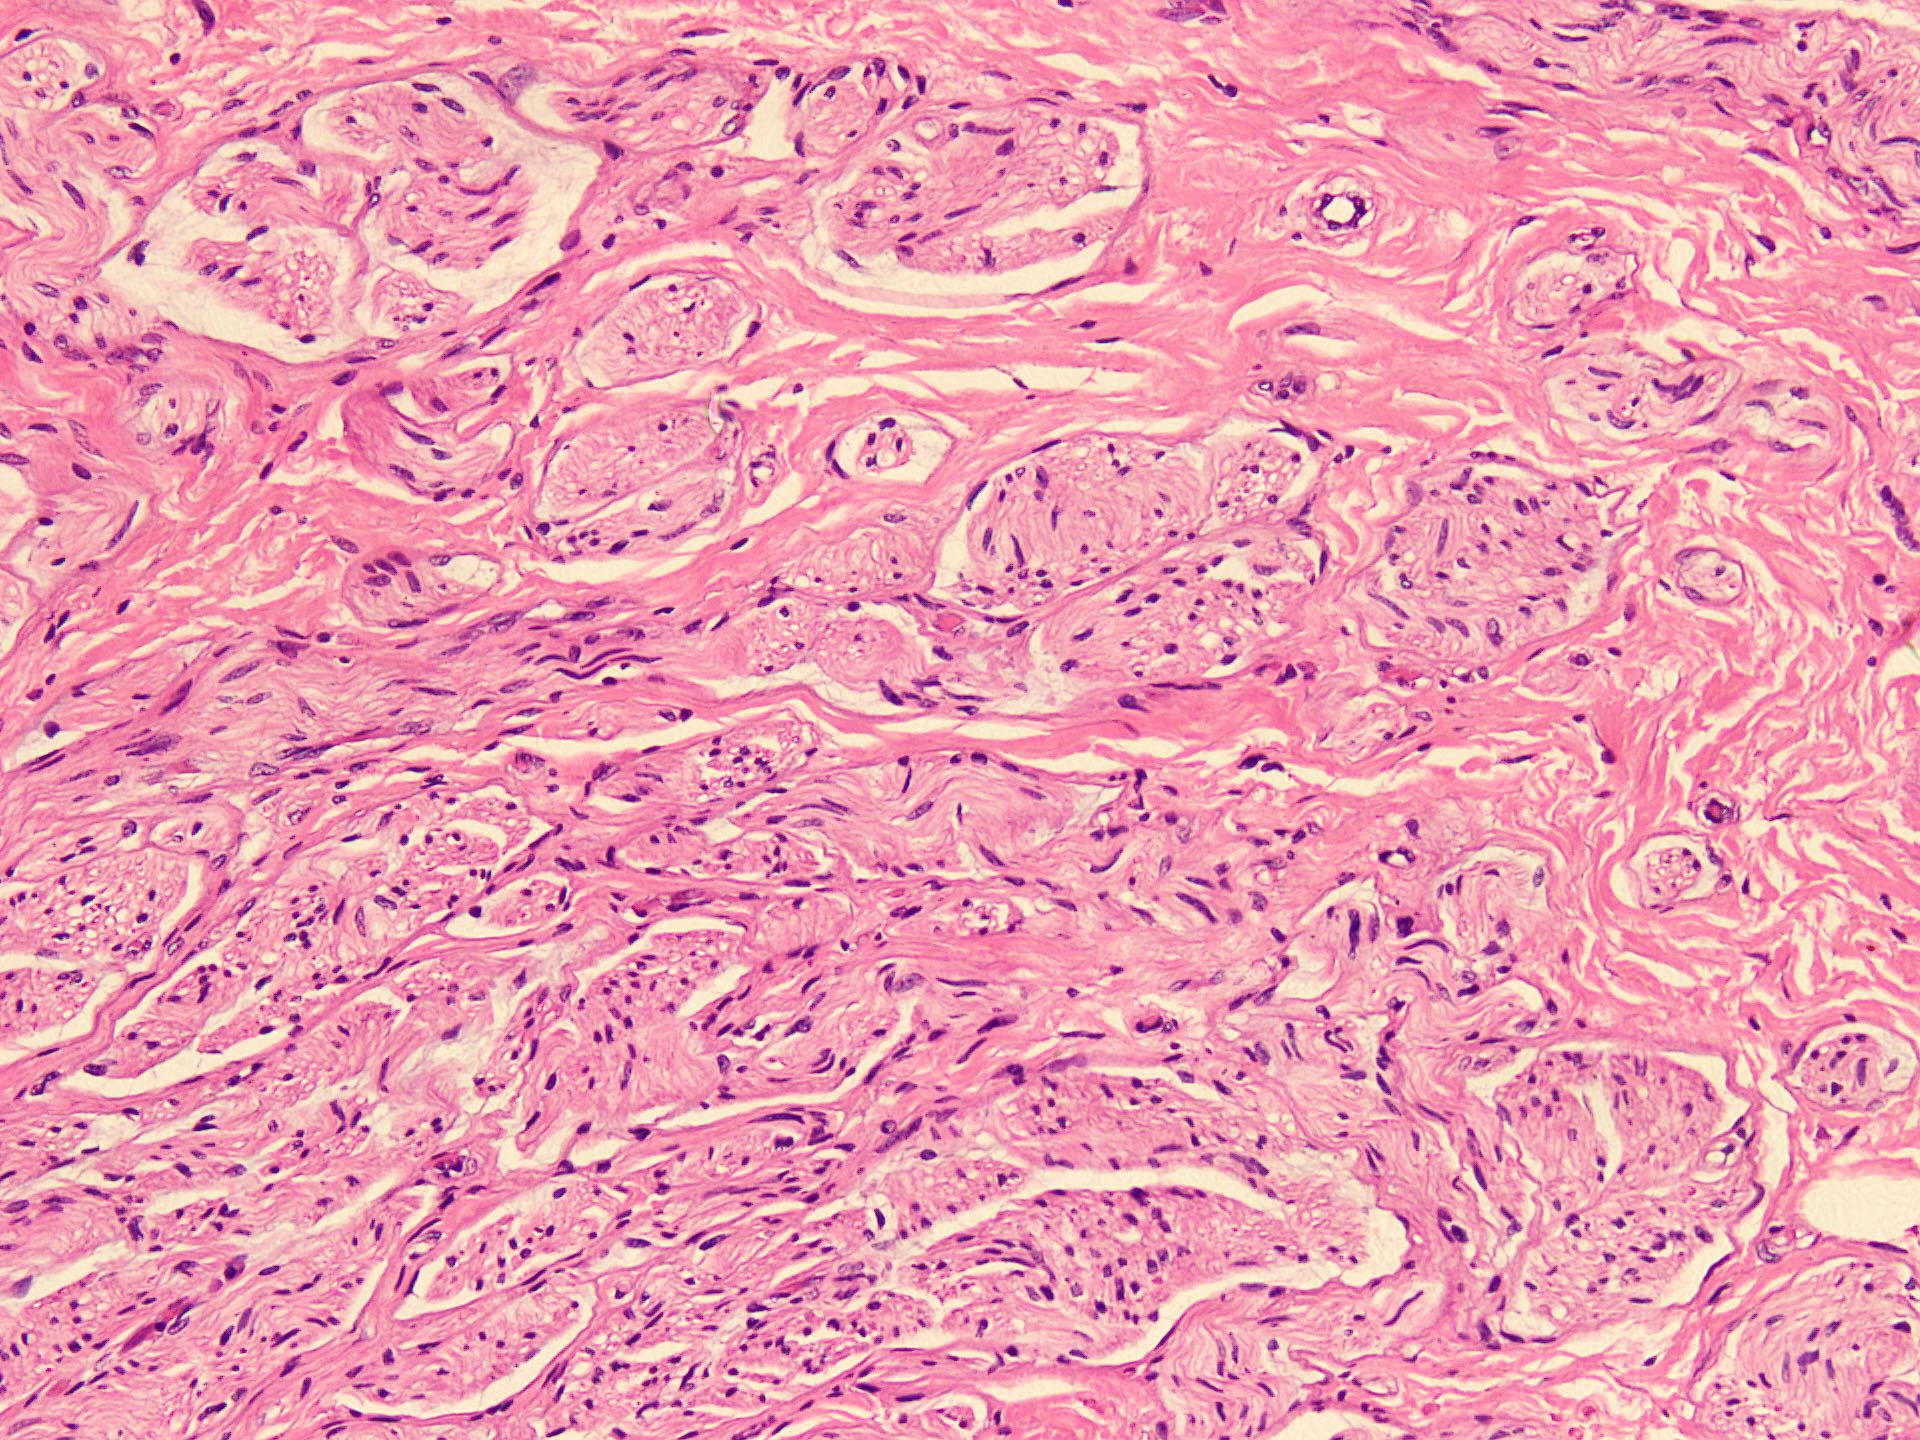

Microscopic (histologic) description

- Circumscribed, unencapsulated spindle cell proliferation arranged in short bundles comprised of axons, Schwann cells, endoneurial cells and perineurial cells (World J Clin Cases 2020;8:3821, Acta Biomed 2020;91:122, StatPearls: Neuroma [Accessed 21 September 2022])

- Peripheral palisading is not present (World J Clin Cases 2020;8:3821)

- Prominent scar tissue with dense collagen may be present (Acta Biomed 2020;91:122, StatPearls: Neuroma [Accessed 21 September 2022])

- Dystrophic calcifications are rarely present (Acta Biomed 2020;91:122)

Microscopic (histologic) images

- Microscopy: The sections examined show a circumscribed, unencapsulated lesion composed of variable sized, closely packed nerve bundle along with scar tissue in the background.